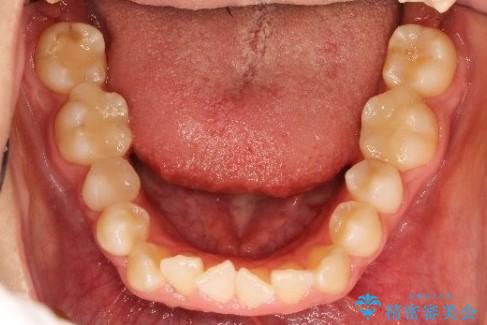

- 前歯の凸凹を主訴に来院されました。

非抜歯の範囲でできるだけ前歯を下げることを希望されたため、IPRと臼歯部の遠心移動を行い治療を行いました。当初はインビザラインで治療を行っておりましたが、使用時間を十分に確保できないことで途中からワイヤーを使用しております。